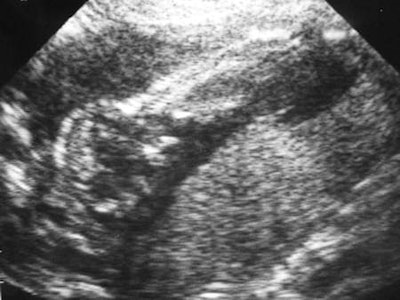

In 1956, Donald and Brown were joined by John MacVicar as a registrar in training. The three of them made an intensive investigation into the value of ultrasound in differentiating between cysts, fibroids, and other abdominal tumors. Ian Donald, John MacVicar, and Tom Brown appeared in print in Lancet on 7 June 1958 under the somewhat dry title of "Investigation of abdominal masses by pulsed ultrasound." This is probably the most important paper on medical diagnostic ultrasound ever published. In more than nine pages it described the experience of 100 patients with 12 illustrations of B-mode sonograms of the gravid uterus, ovarian cysts, fibroids, and ascites, as well as normal and pathological conditions. The safety of diagnostic ultrasound also was discussed, and this was to be a continuing concern for Donald.

In 1959, Ian Donald determined that echoes could be obtained from the fetal head, and his group used head measurement to assess fetal size and growth. The new Queen Mother's Hospital opened in Glasgow in 1964 (described by newspapers as a sort of holiday camp!), and fetal cephalometry became the standard method to assess intrauterine growth.